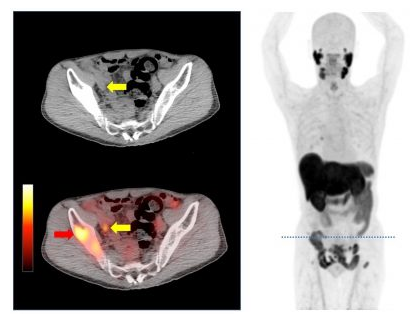

画像はリリースより

これまで、前立腺がんの再発・転移検索は主にCT検査や骨シンチグラフィーで実施されていたが、病変の検出感度が十分でないという課題があった。F-18 PSMA-1007を用いた PET臨床研究は、成人男性で前立腺がんと診断され、全身の転移検索を行う患者、または治療後に再発や転移が疑われる患者など50例を対象とし、F-18 PSMA-1007標識のPETおよびCT検査が行われる。従来の転移評価検査であるCTや骨シンチと比較して、PSMA-PETによる診断能を評価し、詳細な病態解明を行う。実施期間は2019年9月1日~2022年3月31日。1例目は2019年9月3日に行われた。